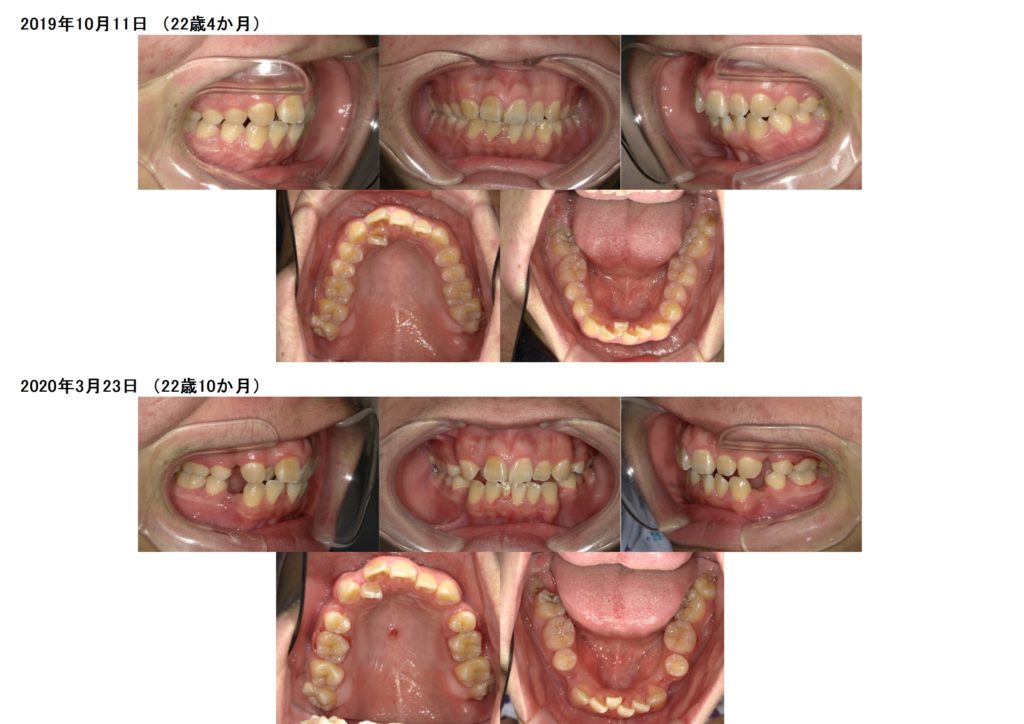

今回は マウスピースを使用し上下抜歯の治療例です。

上の口腔内写真を見ていただくと分かるように、歯が1本ずつ中に入っていますよね。

この患者様は上下4番目の歯を抜歯してマウスピースにて治療をしました。